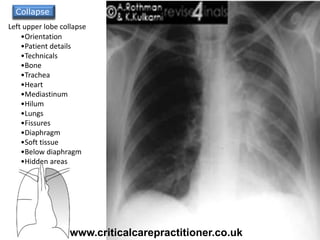

•Orientation

•Patient details

•Technicals

•Bone

•Trachea

•Heart

•Mediastinum

•Hilum

•Lungs

•Fissures

•Diaphragm

•Soft tissue

•Below diaphragm

•Hidden areas

Collapse

Left upper lobe collapse